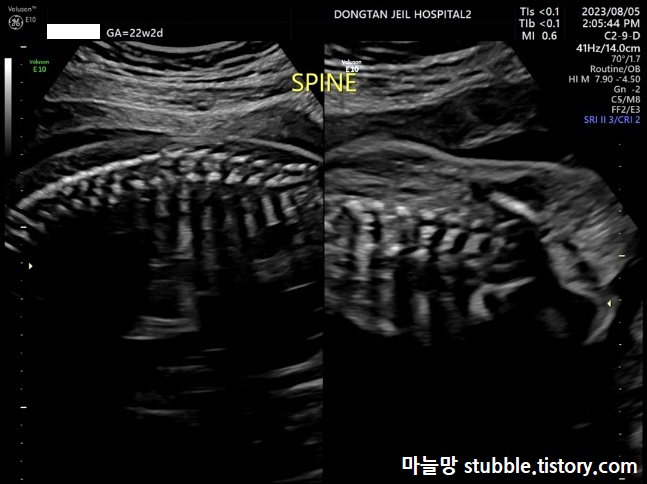

6. 척추뼈가 잘 형성되었는지의 여부 (SPINE)

척추뼈는 옆으로 봤을 때 3줄, 정면으로 봤을때 2줄로 보이면 정상이라고 들었던 것 같아요. (기억이 가물)